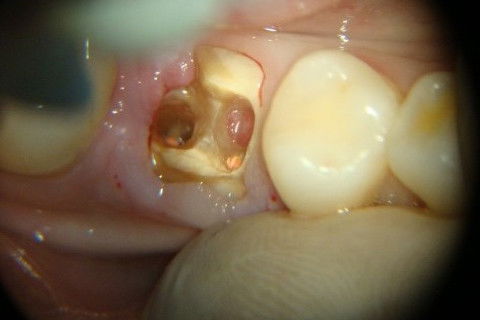

Retratamento de Canal, Tratamento de Perfuração, Restauração Provisória com Resina, Núcleo e Provisório.

RETRATAMENTO DE CANAL, TRATAMENTO DE PERFURAÇÃO, RESTAURAÇÃO PROVISÓRIA COM RESINA, NUCLEO E PROVISÓRIO.